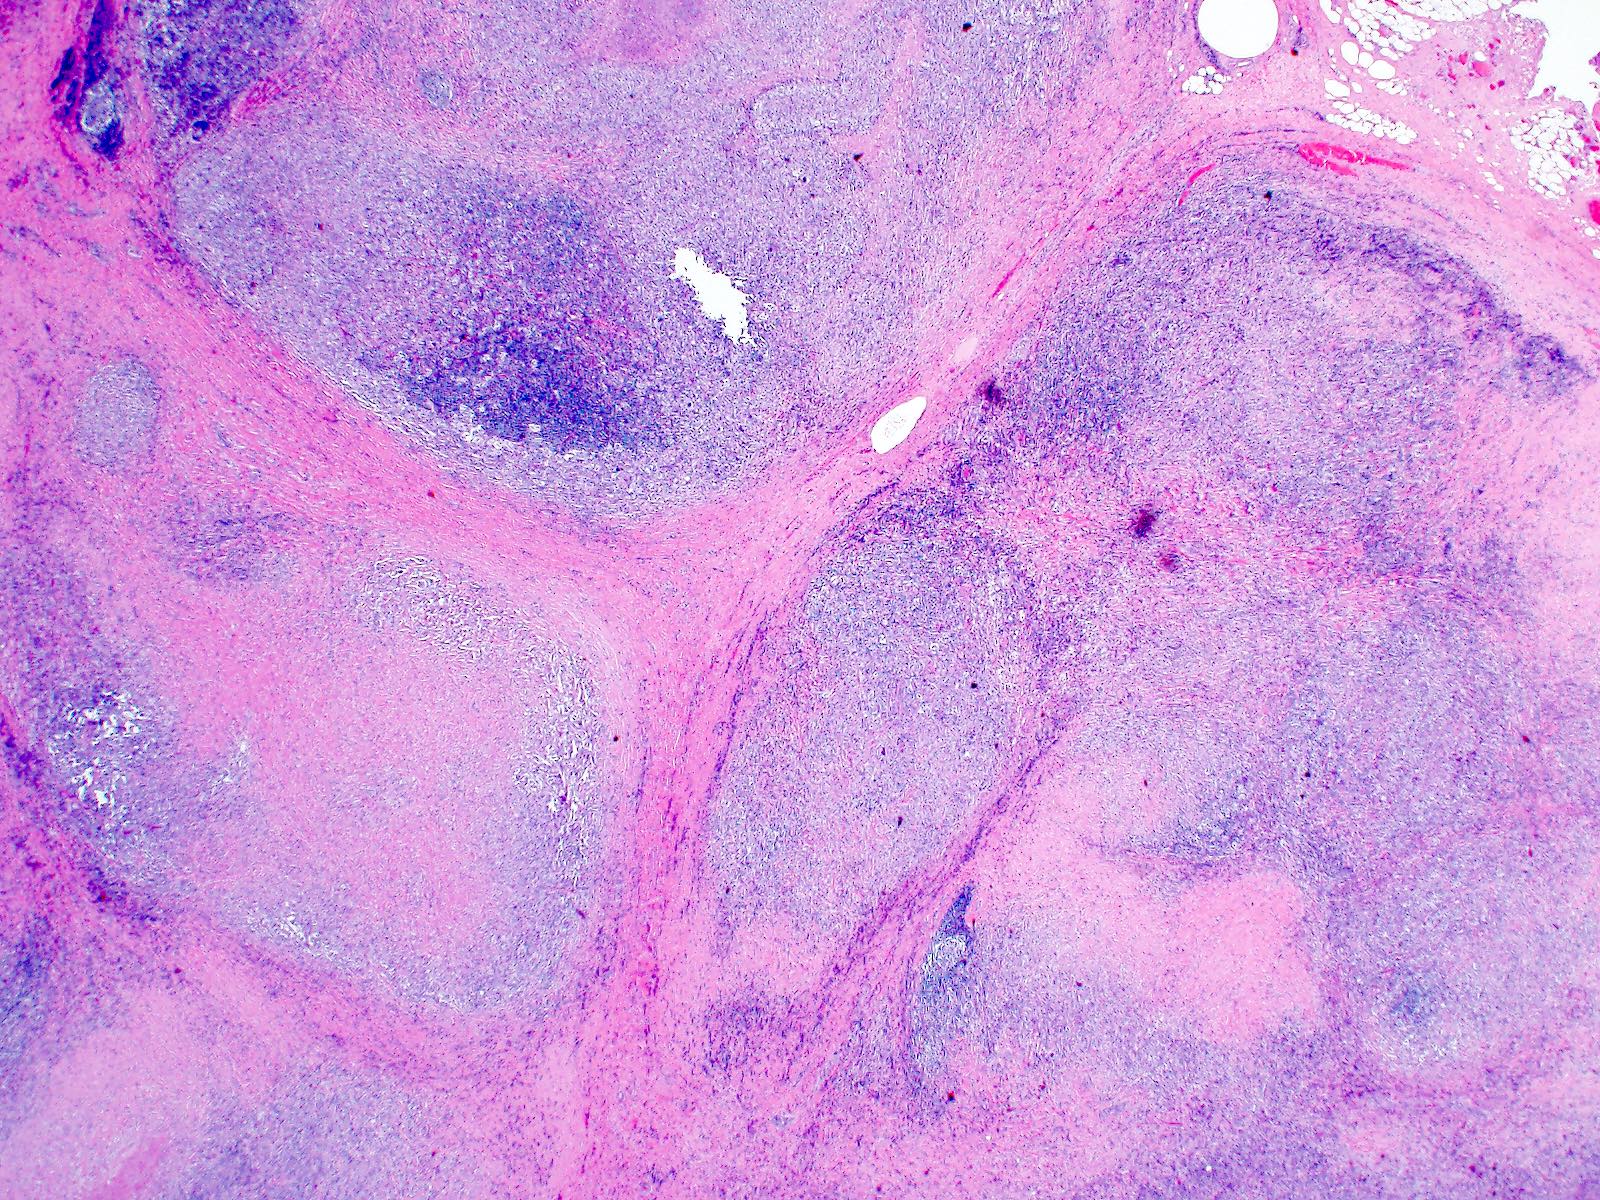

Discover the essential tests for lymphoma cancer used for accurate diagnosis. Learn how medical professionals utilize biopsies, blood tests, imaging scans like PET and CT, and bone marrow exams to detect cancer cells. Understanding these diagnostic procedures is vital for early detection, staging, and determining the most effective treatment plan for improved patient outcomes.

Read full article: Tests For Lymphoma Cancer